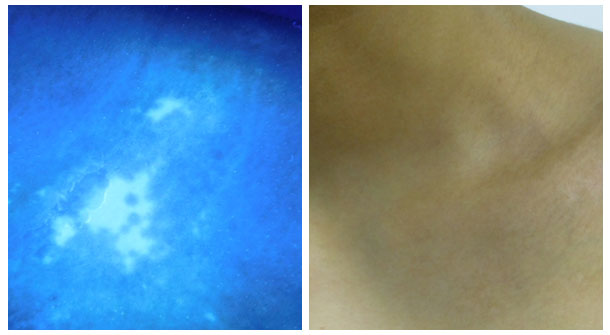

【治疗案例】:姓名:浩浩(化名) 年龄:18岁 病情:由牛皮癣引发的白癜风。

病情描述:在发现身体上出现白斑、白点后,就在当地县医院进行治疗,用药控制半年不理想,后转至市医院治疗一年,当时部分白斑恢复较快,但近期发现白斑恢复慢并且有了新发白斑,疾病的折磨让患者着急万分。后来经朋友介绍,来到了石家庄远大医院。

治疗过程:来我院后,医生先为浩浩做了系统检查如伍德灯检查、皮肤ct检测等。通过检查发现患者锁骨、胸部、腹部、肢端部位、腰部、双胯等多部位存在白斑,随后在多项白斑检测的结果下诊断患者浩浩的病情为进展期白癜风。